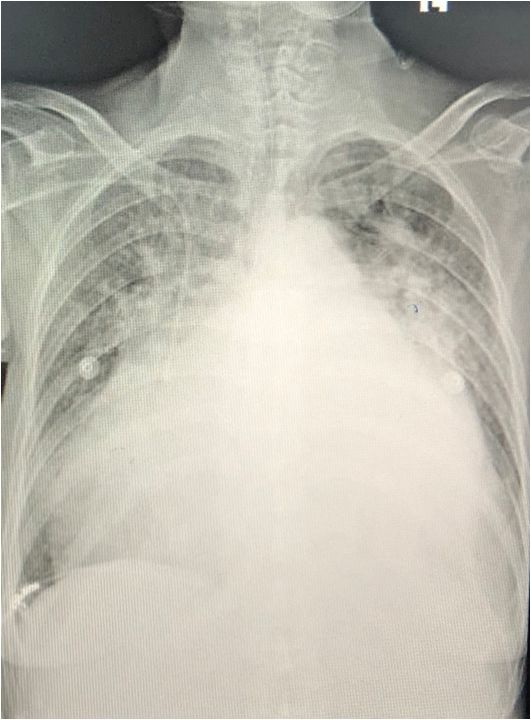

心影显著增大

肺淤血并炎症

纵膈增宽